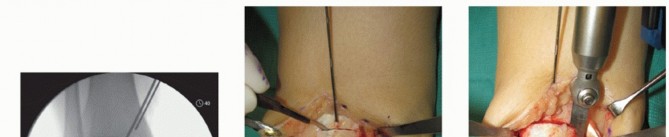

Anterior ankle arthrotomy (TECH FIG 1A)

Defines anterior joint margin for safe performance of medial malleolar osteotomy

Allows partial visualization of the OLT and allows confirmation that there is no diffuse articular cartilage degeneration

Open the posterior tibial tendon sheath-flexor retinaculum, directly on the posterior margin of the tibia and medial malleolus (TECH FIG 1B). Protect the posterior tibial tendon: It rests in a groove immediately posterior to the tibia and is at great risk with a medial malleolar osteotomy.

- TECH FIG 1 • A. Medial incision and anterior ankle arthrotomy. B. Opening of the posterior tibial tendon sheath. C. Predrilling of medial malleolus. Kirschner wire for trajectory of medial malleolar osteotomy has already been inserted and its position confirmed with fluoroscopy. D. Fluoroscopic image demonstrating Kirschner wire being used as a guide to direct the saw. E. The periosteum is scored perpendicular to the tibial shaft, at the level of the osteotomy. F. Medial malleolar osteotomy. Care must be taken to protect the posterior tibial tendon. (continued)

Predrill the medial malleolus across the proposed osteotomy site (TECH FIG 1C).

We routinely use two small fragment malleolar screws and predrill with the corresponding drill. Obtain fluoroscopic confirmation that the drill bits are in the proper trajectory.

Place a Kirschner wire obliquely to define the trajectory of the medial malleolar osteotomy (TECH FIG 1C).

Place it slightly proximal to the desired osteotomy so it can function as a guide but not interfere with the saw (TECH FIG 1D).

Confirm the optimal Kirschner wire trajectory with intraoperative fluoroscopy.

Determine a plane for the osteotomy in the anteroposterior (AP) plane that is perpendicular to the longitudinal axis of the tibia. We find it helpful to score the osteotomy in the periosteum from anterior to posterior to determine this level (TECH FIG 1E).

With a microsagittal saw oriented correctly in both planes, the osteotomy is initiated (TECH FIG 1F).

Obtain intraoperative fluoroscopy shortly after initiating the osteotomy; leave the saw blade in place to confirm proper trajectory. If incorrect, a subtle adjustment is still possible (TECH FIG 1G).

Continue the osteotomy with the saw to the subchondral bone and then complete the osteotomy with a chisel.

A fluoroscopic spot view allows the surgeon to confirm that the osteotomy is appropriate and is not violating the talar cartilage.